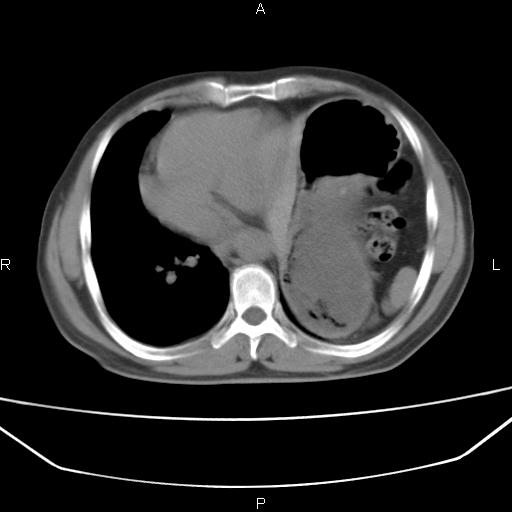

患者,男。50岁。近几日有咳嗽症状,无其他不适,既往病史无,考虑膈疝。请前辈们看看指导指导。

膈膨升,左下肺通气不良,膈肌好像还完整。

考虑左侧膈疝。

左侧膈疝。

符合隔膨升,膈肌较完整。